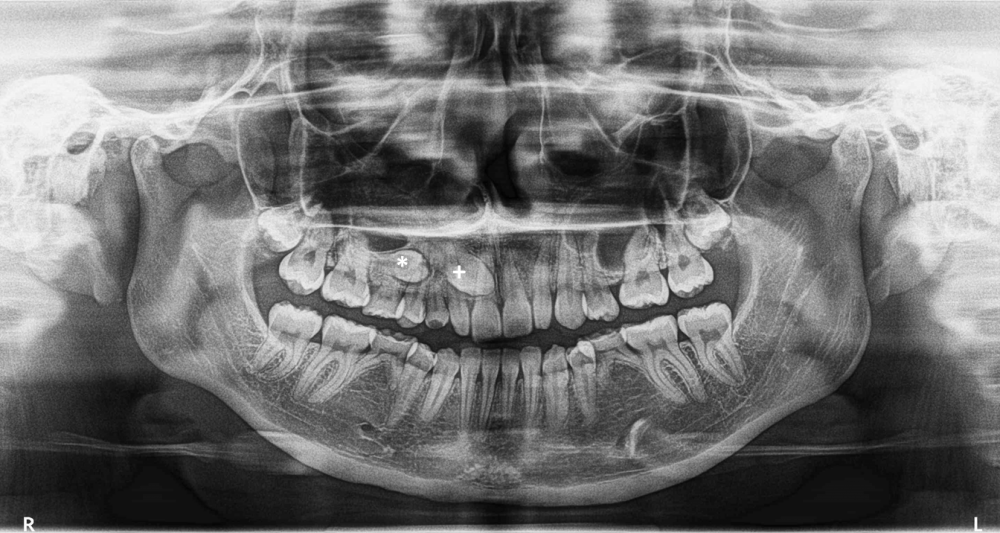

Cirugía de terceros molares impactados (cordales o muelas del juicio).

• Radiografía panorámica.